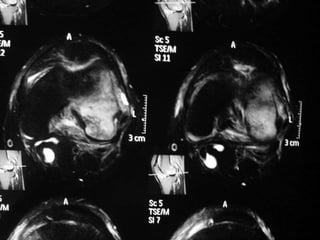

The document presents a detailed case study of a patient with transient osteoporosis of the hip (TOH) and spontaneous osteonecrosis of the knee (SONK) treated at Choithram Hospital & Research Centre in India. Over 20 years, the patient experienced multiple episodes of TOH and SONK with no history of trauma or co-morbidities, resulting in resolutions and recurrences of conditions. The information is intended for orthopedic surgery students and highlights personal experiences and case collections, with a disclaimer regarding content usage and potential controversies.